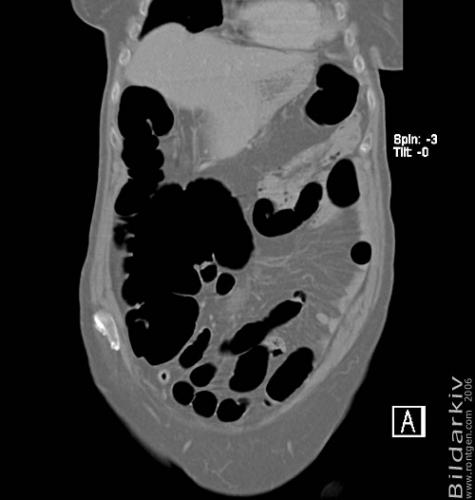

CT colon 18

Datortomografi av tjocktarmen (colon) med infunderad luft i tarmen samt med kontrast i blodbanan. Koronar bildserie.

CT multislice 16